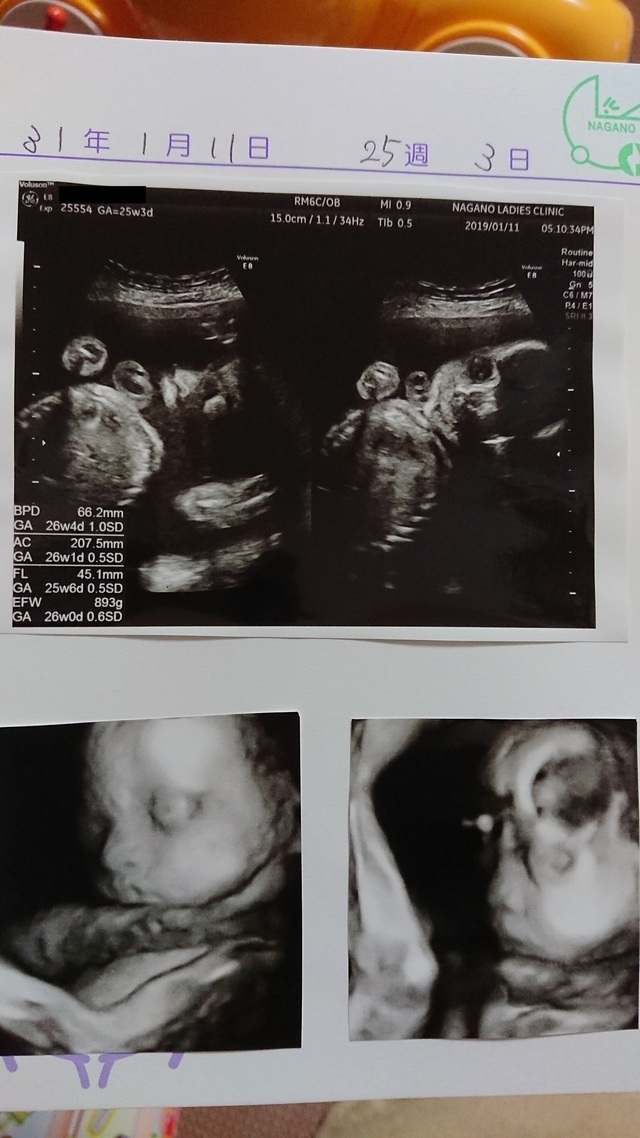

25週3日(25w3d・男の子)|イリ(*・・) さん(29歳)

エコー写真撮影時のエピソード:

今までずっと手で顔を隠していて、やっと撮れた顔がこれでした。凄く怒っているように見えて、笑ってしまいました。(笑)

きっと恥ずかしがって顔を隠していたのに、撮られてしまったから怒ったのかな?など、夫婦で会話がはずみました。